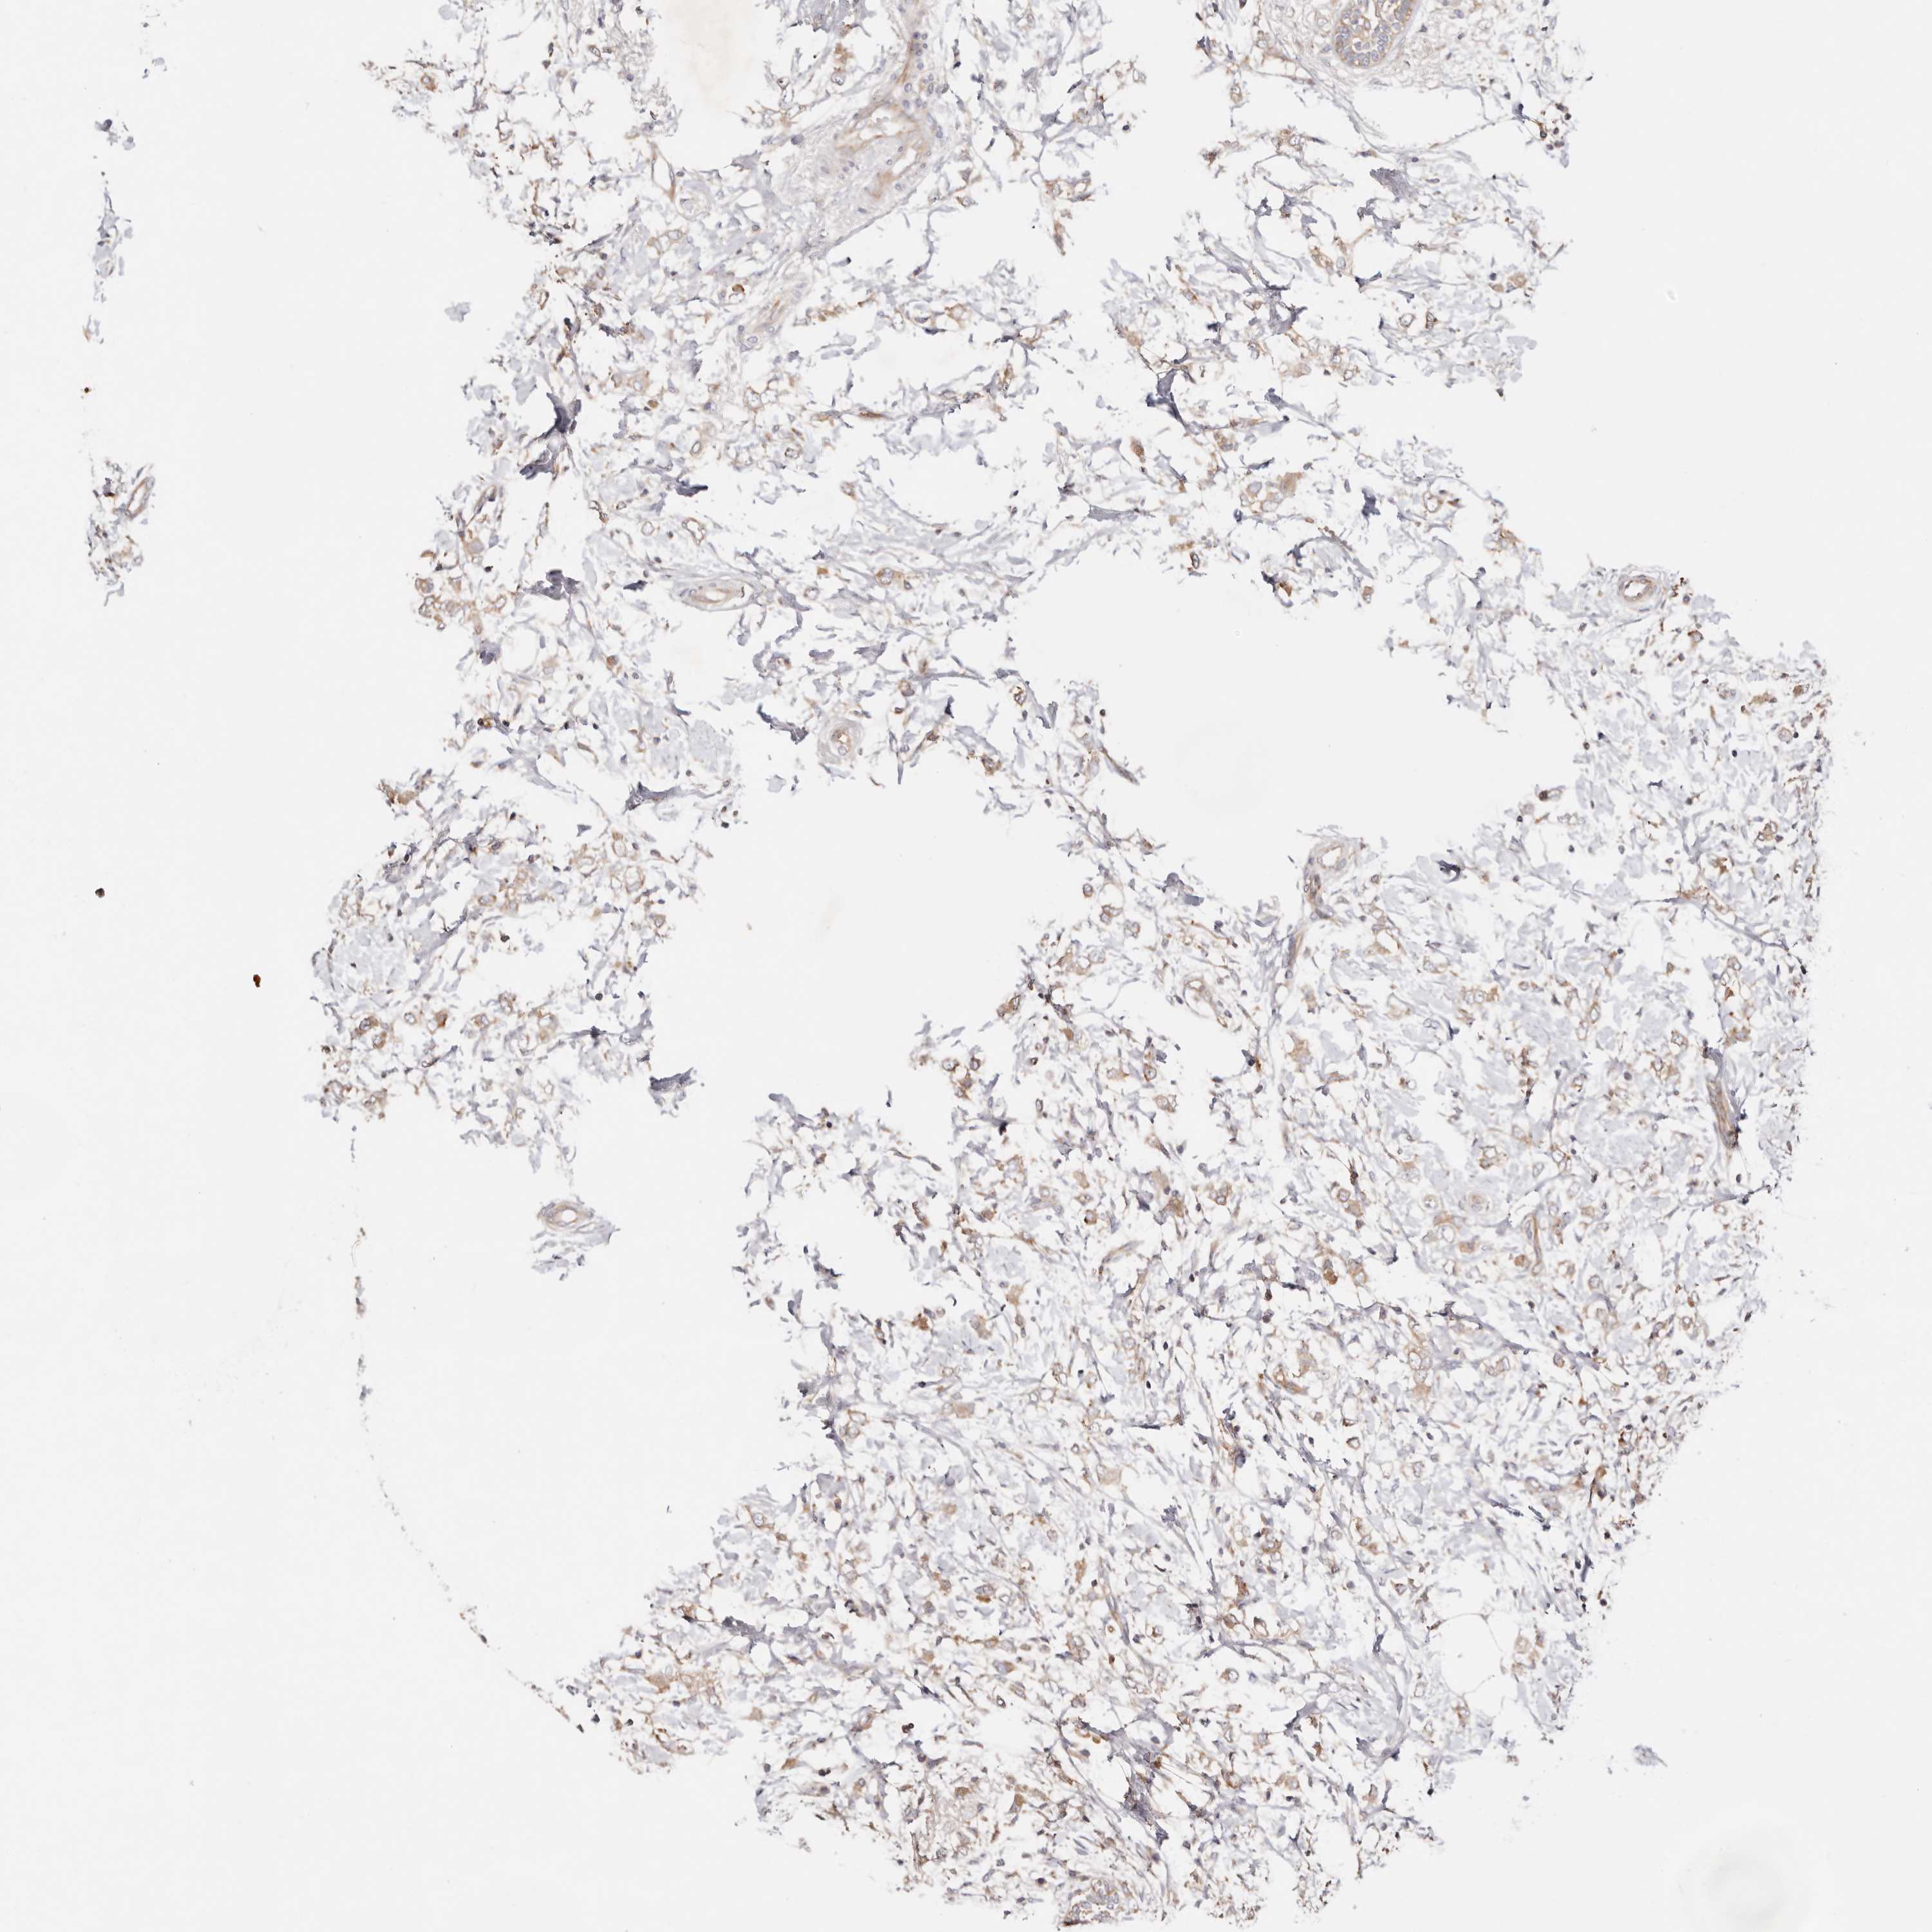

CANCER BREAST CANCER Show tissue menu

BRCA TCGA BRCA VALIDATION PROTEIN EXPRESSION